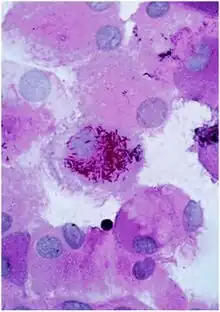

| Tropheryma whipplei bacteria in human macrophages | |

Individuals who are most susceptible to Whipple's disease are those with decreased ability to perform intracellular degradation of ingested pathogens or particles, particularly within macrophages. Several studies indicate that defective T-lymphocyte function may be an important predisposing factor for the disease.[10]